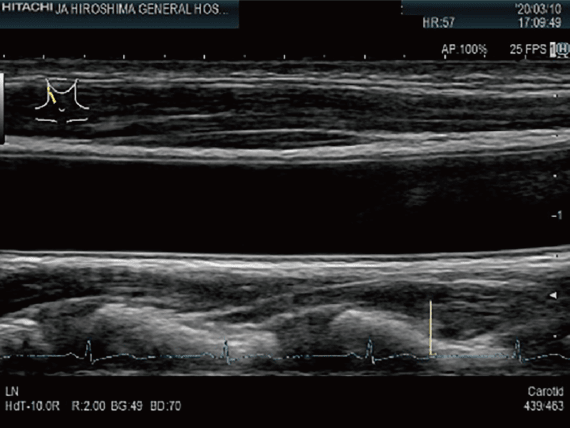

頸動脈超音波検査

胸頸部より超音波を照射し,頸動脈を観察する検査です。動脈硬化やプラークによる血管狭窄・閉塞などの評価に用いられます。